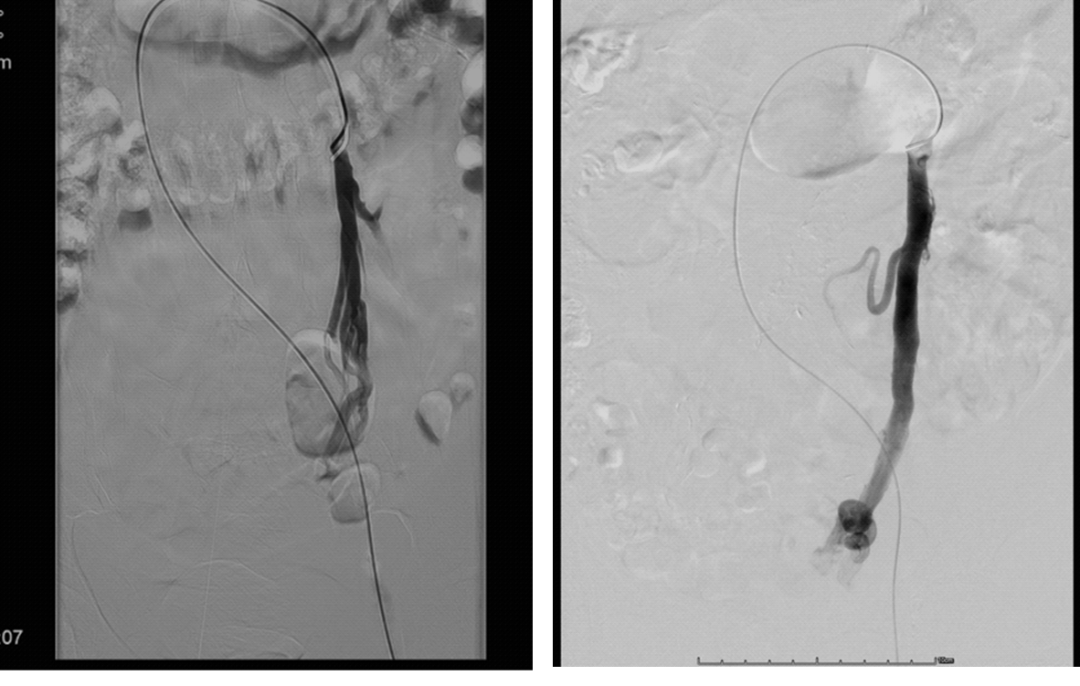

介入治疗技术演进

同轴技术

可调弯鞘+Cobra2导管+微导管

传统三明治技术(sandwich)

弹簧圈+泡沫硬化剂

大于目标血管(>2mm)1-3mm

静脉造影+Valsalva maneuver

Ovarian/Internal iliac/Vulvar/Vaginal Varicosities

Sandwich技术优化-节约版

GLUBRAN替代Onxy;

双股静脉入路:可调弯鞘解决反流支;

减少可控圈以及微导管使用;

减少费用;

减少照射;

减少移位;

减少复发;

需解决技术问题:液体栓塞材料溢流。

示例(D-IIV)

示例(LOV+LCV)